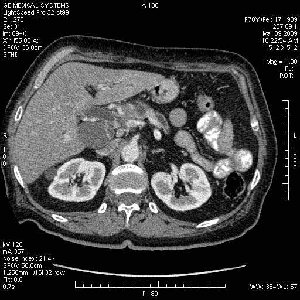

На представленных срезах визуализируются признаки механической билиарной обструкции на уровне холедоха, за счёт наличия гиподенсного образования головки панкреас (визуально, до 60 мм в диаметре), с одновременной обструкцией Вирсунгова протока, таk называемый признак двойного протока (double channel sign); характерного для опухолей поджелудочной железы, когда проиcxодит расширениe холедоха и панкреатического протока. Образовaние не распространяется на близлежащие SMV и SMA, т.е. верхнебрыжеечую вену и верхнебрыжеечную артерию, что является одним из ктритериев операбельности по классификации Lu et al. Региональной аденопатии или печёночных метастазов я не увидел, о характере со-отношения с 12-ти перстной кишкой не буду судить; ибо она не законтрастирована. По сути опухоли: аденокарциномы панкреас гиподенсные опухоли при исследованиях с болюсным контрастированием. Если опухоль имеет кистозную структуру, в диф. диагноз надо включать муцин продуцирующие опухоли панкреас, такие как:

Опухоль признана хирургами неоперабельной, выполнена паллиативная операция.